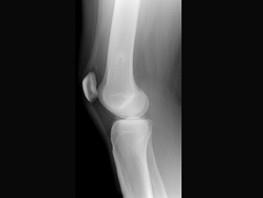

问题 患者,女性,39岁。发现左大腿下段后部有一包块,质较硬,无明显疼痛感觉,请结合所提供的图像,选择最佳选項 ( )

选项 A、骨软骨瘤 B、骨瘤 C、软骨瘤 D、骨肉瘤 E、软骨肉瘤

答案 A